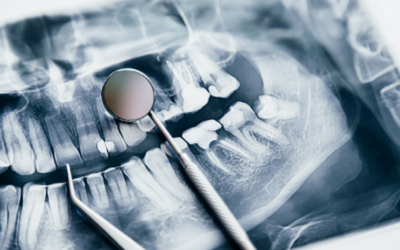

Do All Wisdom Teeth Need to Be Removed? What Dentists Recommend

One of the most common questions patients ask is, “Do all wisdom teeth need to be removed?” The answer depends on your situation. At Emu Plains...

Signs You Might Need Your Wisdom Teeth Removed

Your wisdom teeth are the last set of molars to emerge, typically between the ages of 17 and 25. While some people have no problems with them, for...